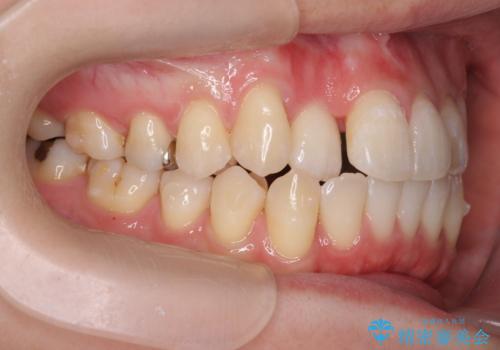

引っ込んだ前歯を並べたい マウスピースと部分ワイヤーのコンビネーション矯正

- 引っ込んで生えてしまっている前歯を並べたい、と矯正治療を希望され来院されました。

まずマウスピース矯正インビザラインシステムで、引っ込んだ歯が並ぶためのスペースを作ったのち、部分ワイヤー矯正を行い短期間での配列を計画します。

このように前歯の部分ワイヤーは引っ込んでしまった前歯や がたつきを素早く改善することができます。